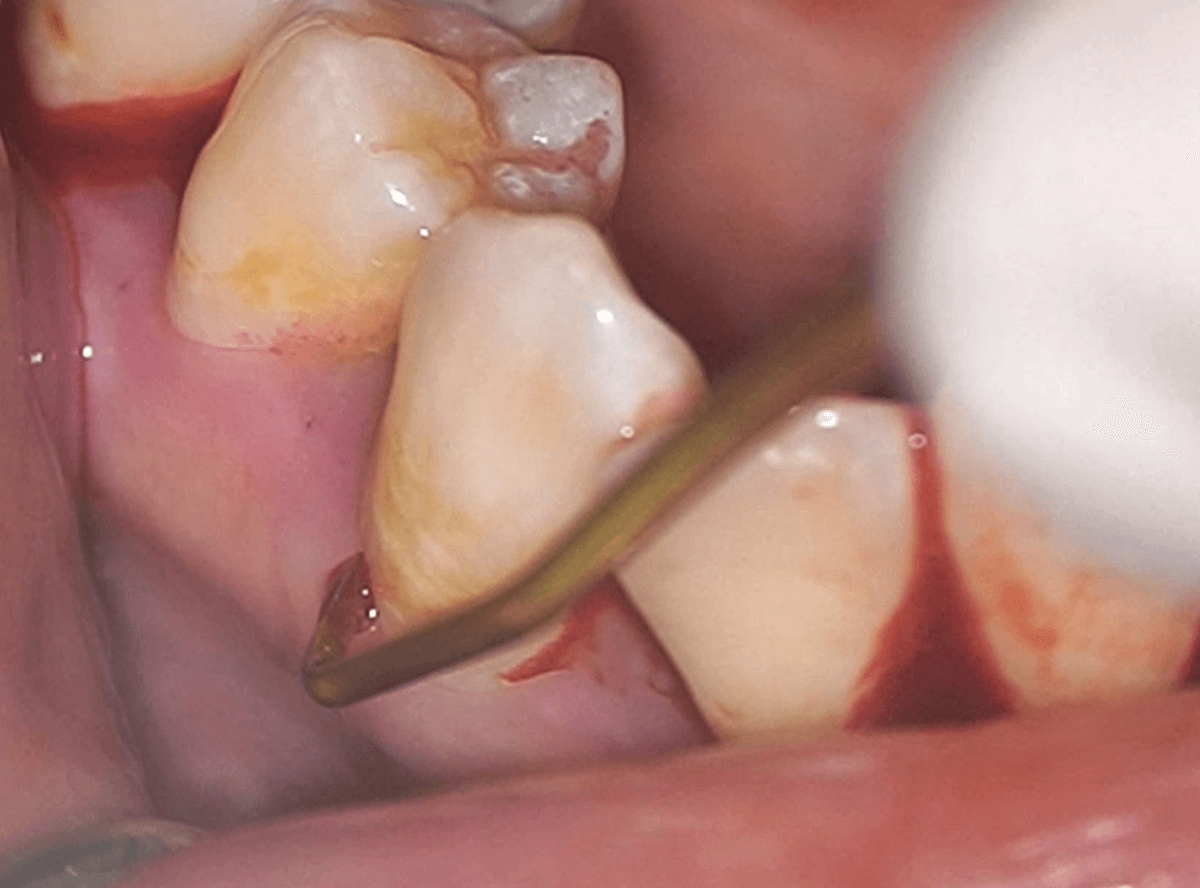

歯周ポケット検査

歯医者さんで「チクチクしますね〜」と言われながら、細い器具で歯ぐきをなぞられる検査を受けたことはありませんか?

これは「プロービング検査(歯周ポケット検査)」といって、歯ぐきの健康状態を調べるための大切なチェックです。

歯周ポケット検査では、こんなことを見ています

① 歯と歯ぐきの「すき間の深さ」

健康な歯ぐきには、歯と歯ぐきの間に1〜3mmくらいの浅いすき間(=歯周ポケット)ですが、歯周病が進行すると、このすき間が4mm以上に深くなっていきます。

★歯周ポケットが深い = 歯ぐきの中で炎症が進んでいるサインです。

② 出血の有無

健康な歯ぐきは、検査しても出血しません。

歯周ポケット検査のときに出血するのは、歯ぐきに炎症がある証拠です。

★出血 = 歯周病の「今」の進行度を示す重要な指標です。

SRP(スケーリング・ルートプレーニング)

歯周病の進行した方を対象に、スケーリング後、さらに歯肉の中に着いた「歯肉縁下歯石」の除去をする処置です。

縁下歯石は、特に歯周病を進行させる原因になります。

縁下歯石は歯茎の中にあるため見えづらく、硬いため、超音波スケーラーに加え、ハンドスケーラーを使って丁寧に除去します。

歯肉の中を触るため、局所麻酔を併用することが多いです。

歯石を除去した歯面は、凹凸のない状態に整え、歯石の再付着を防止します。